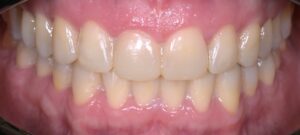

La teoria trova la sua conferma definitiva nella pratica quotidiana del nostro laboratorio. Negli ultimi mesi, abbiamo documentato numerosi casi in cui la Flow Injection Technique ha risolto sfide estetiche complesse con una naturalezza sorprendente.

Dalla chiusura dei diastemi al ripristino di intere arcate usurate, i casi trattati da Dentalstyle dimostrano che è possibile coniugare un approccio ultra-conservativo con un’estetica di altissimo livello. Vedere il paziente sorridere con sicurezza, sapendo che i suoi denti sani sono rimasti intatti, è la soddisfazione più grande per il clinico e per noi tecnici.